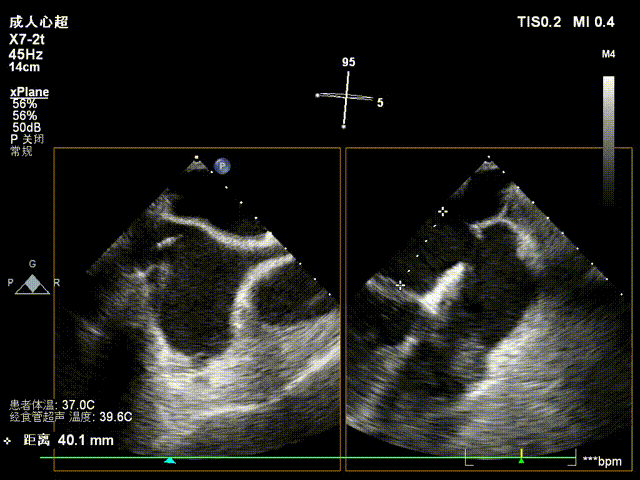

患者取平卧位,消毒铺巾后,穿刺右股静脉后置入6F血管鞘,经食道超声指导下进行房间隔穿刺,穿刺高度约4cm。

房间隔穿刺高度4cm

房间隔穿刺